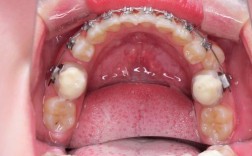

- 关闭拔牙间隙:正畸治疗中常因牙齿拥挤需拔除前磨牙,拔牙后的间隙需通过牵引牙齿向移动关闭,橡皮筋能精准控制牙齿移动方向,避免间隙两侧牙齿倾斜。

| 颌内牵引 | 单一牙弓内牙齿相互牵引(如尖牙向远中移动) | 关闭拔牙间隙、纠正牙齿扭转 | 尖牙远中牵引(将尖牙向口腔后方移动,为前牙排齐腾出空间) |

- 短方形(1/4英寸):最常用,适用于上下颌小范围牵引,如纠正前牙咬合。

- 长方形(3/16英寸):牵引距离较长,适用于磨牙间牵引或关闭大间隙。